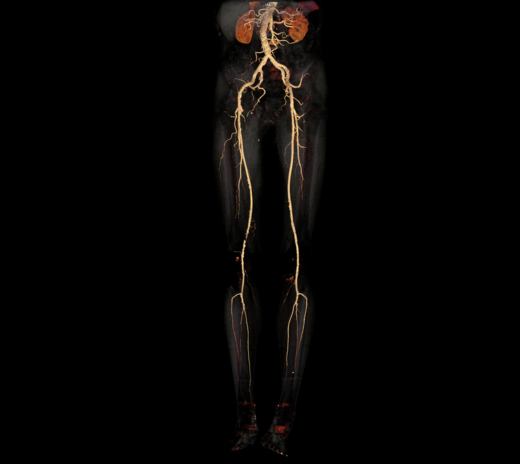

下肢血管

主动脉血管